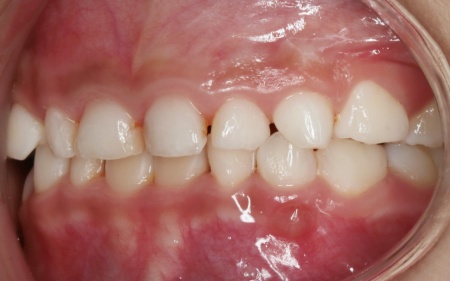

治療前

診断結果 拝見したところ、乳歯が隙間なく密集して生えている状態でした。

通常、乳歯の時期には歯と歯の間に発育空隙(はついくくうげき)と呼ばれる自然な隙間や、犬歯の前後に霊長空隙(れいちょうくうげき)と呼ばれる特徴的な隙間があります。

この隙間は、将来永久歯が生えるために必要なスペースを確保するためのものです。

しかし、患者様はこれらの重要な隙間がほとんど見られませんでした。

今のままでは、今後永久歯が適切な位置に並ぶためのスペースが不足すると考えられます。